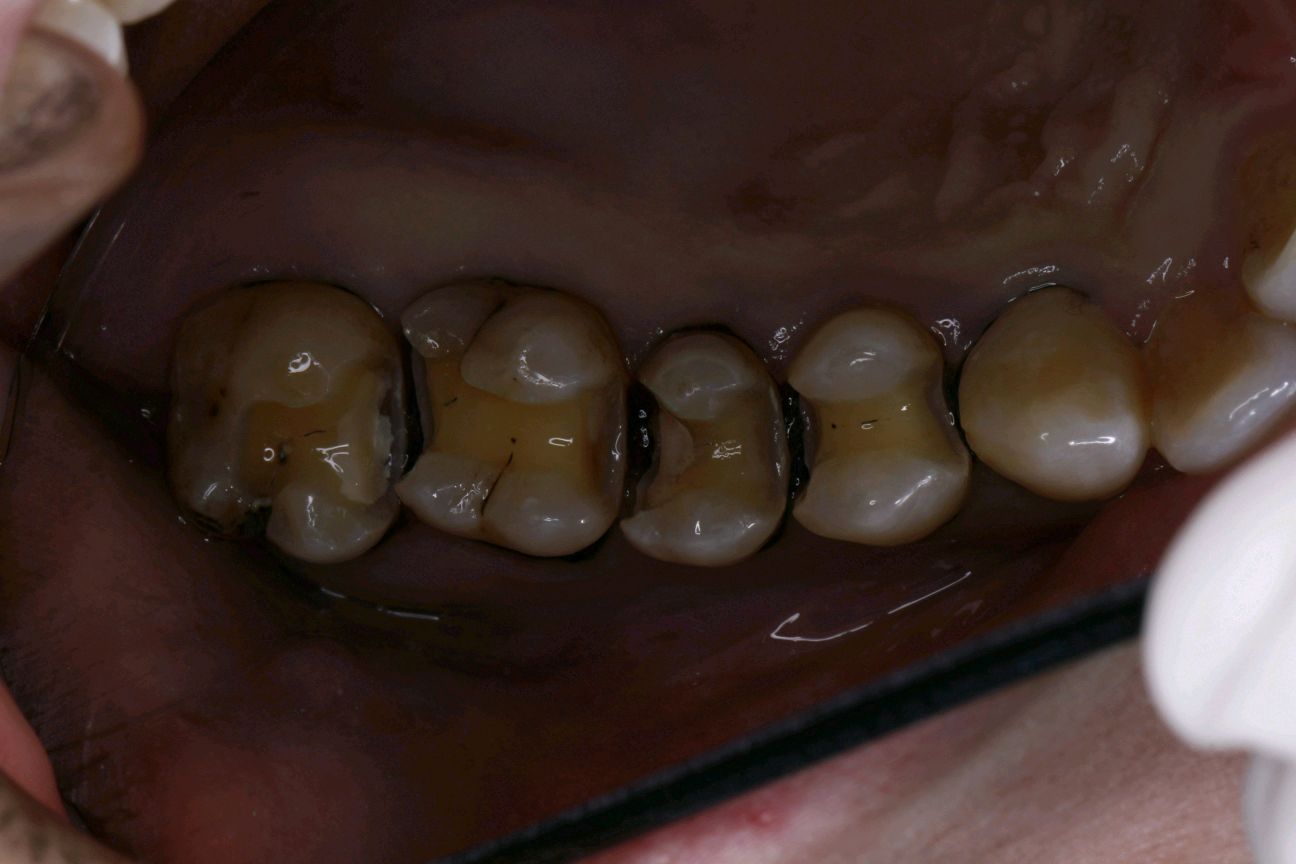

术后